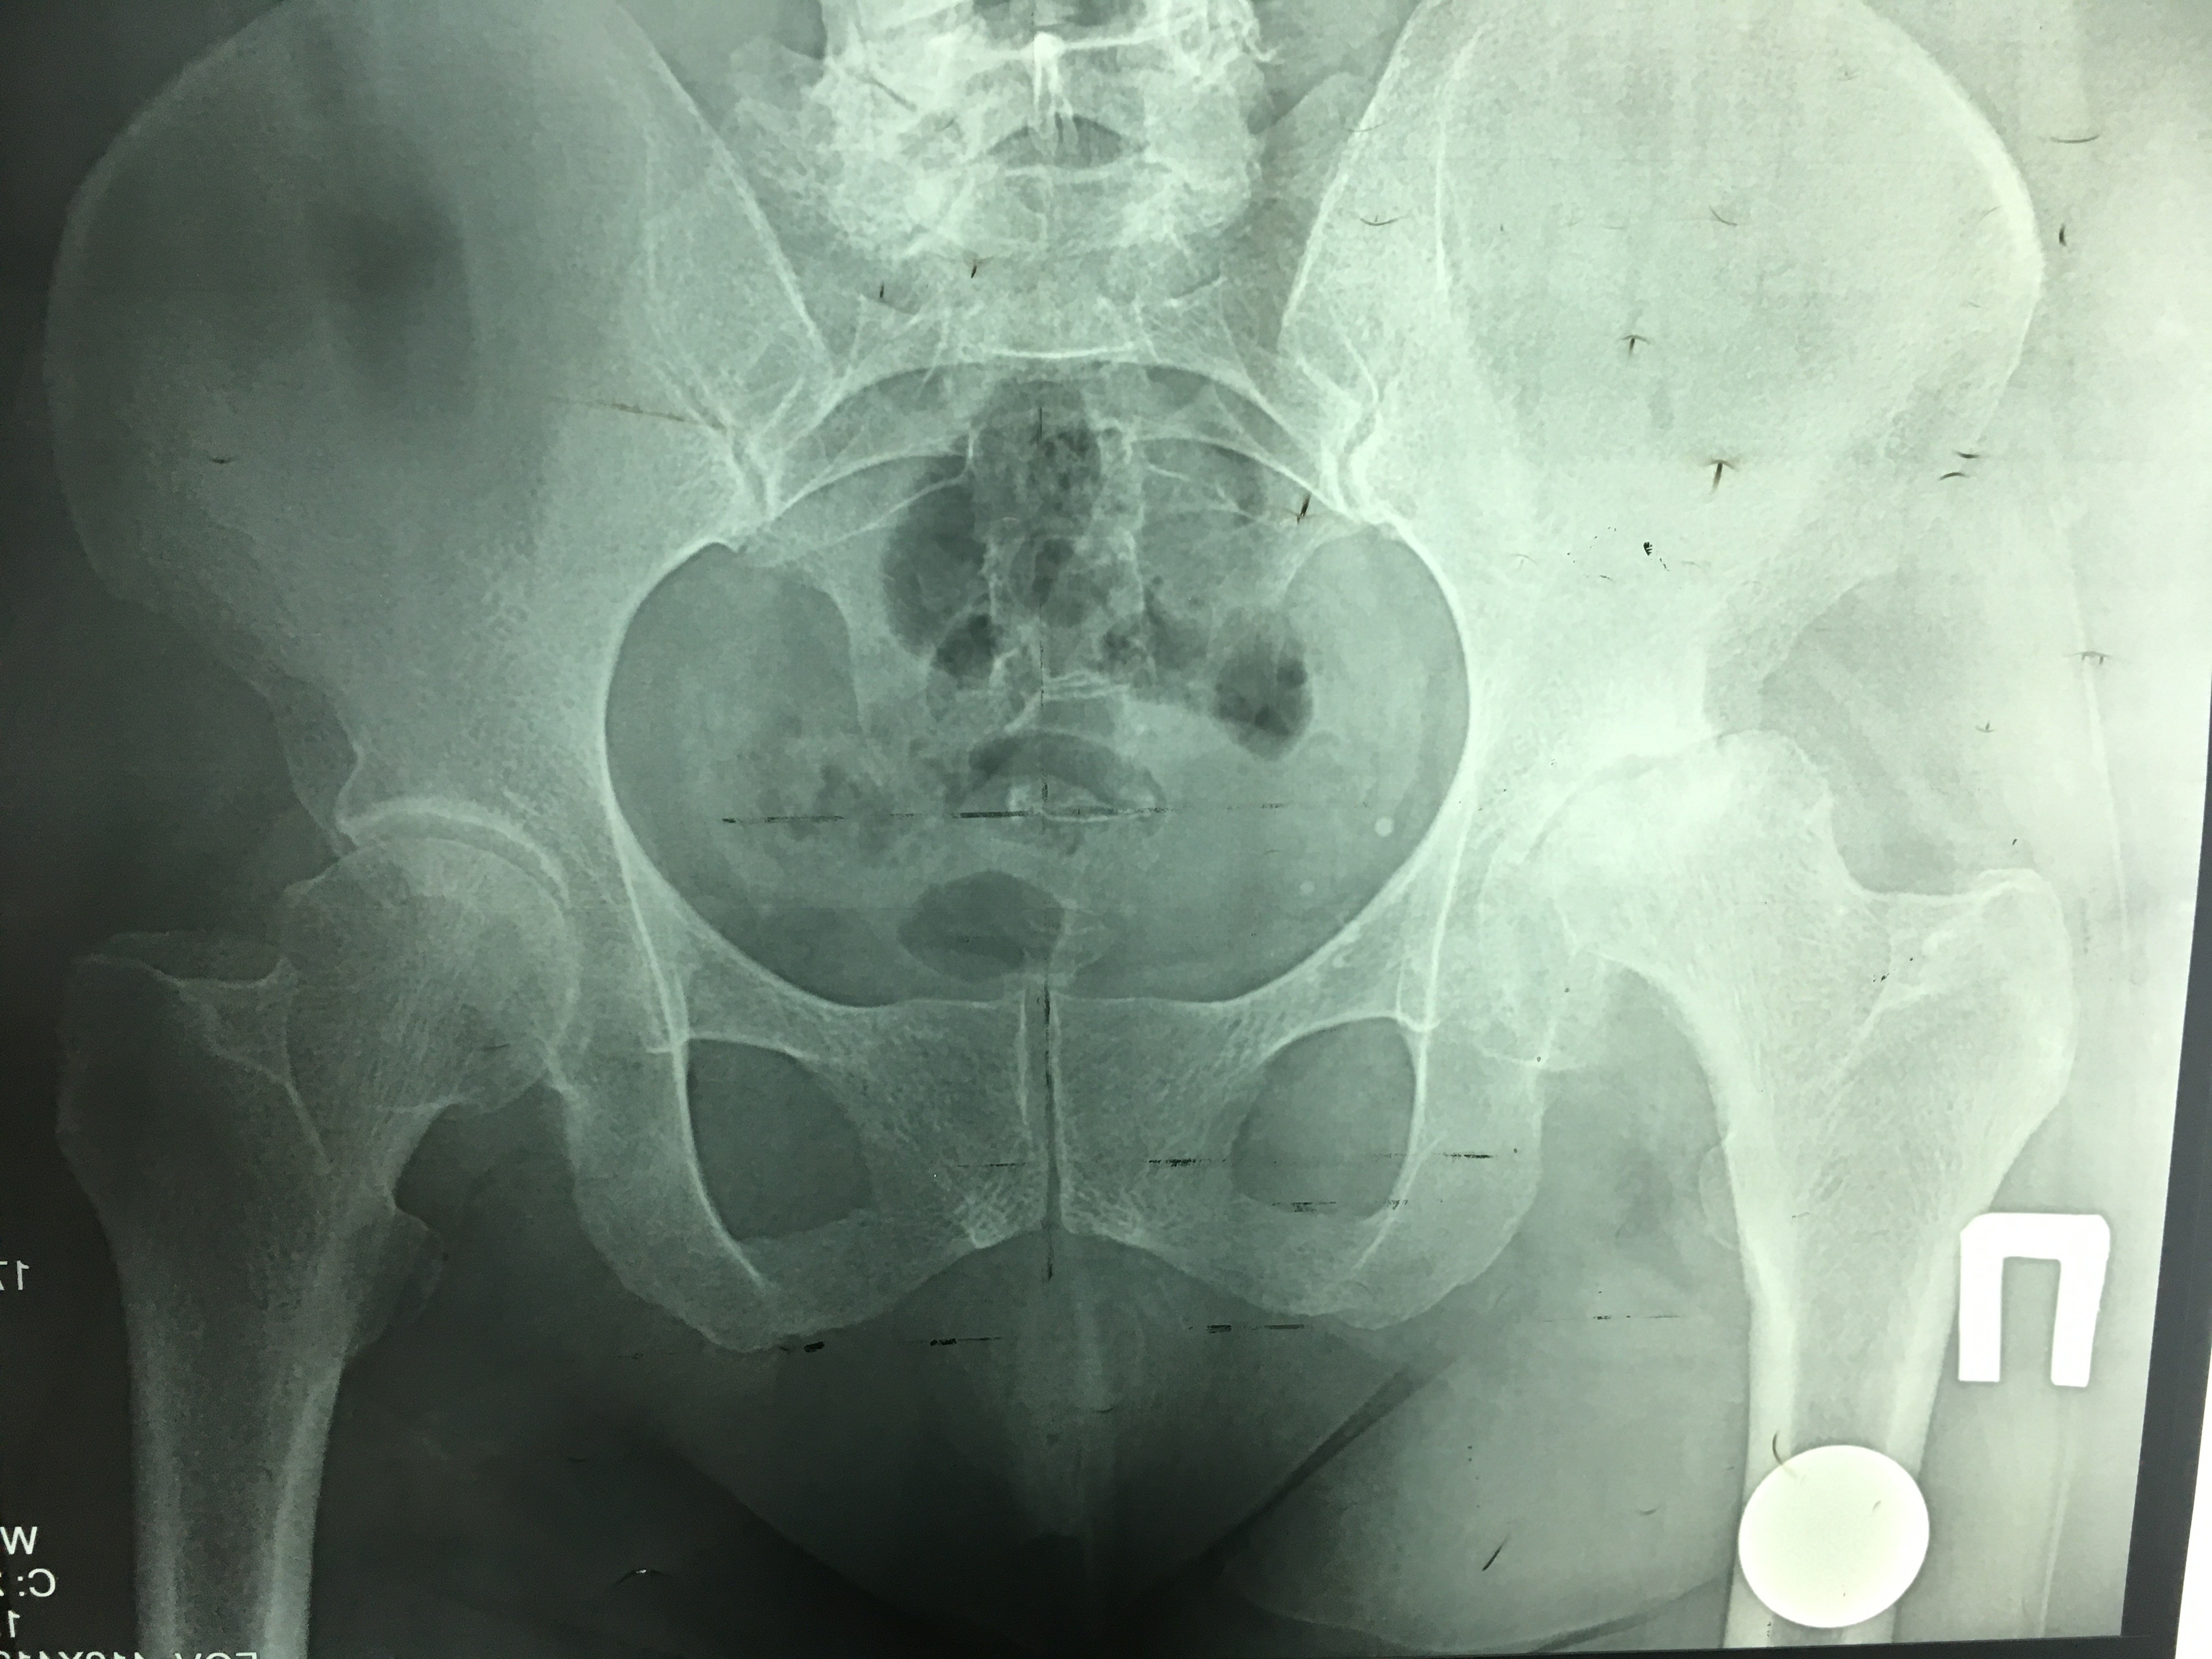

Эндопротезирование тазобедренного сустава